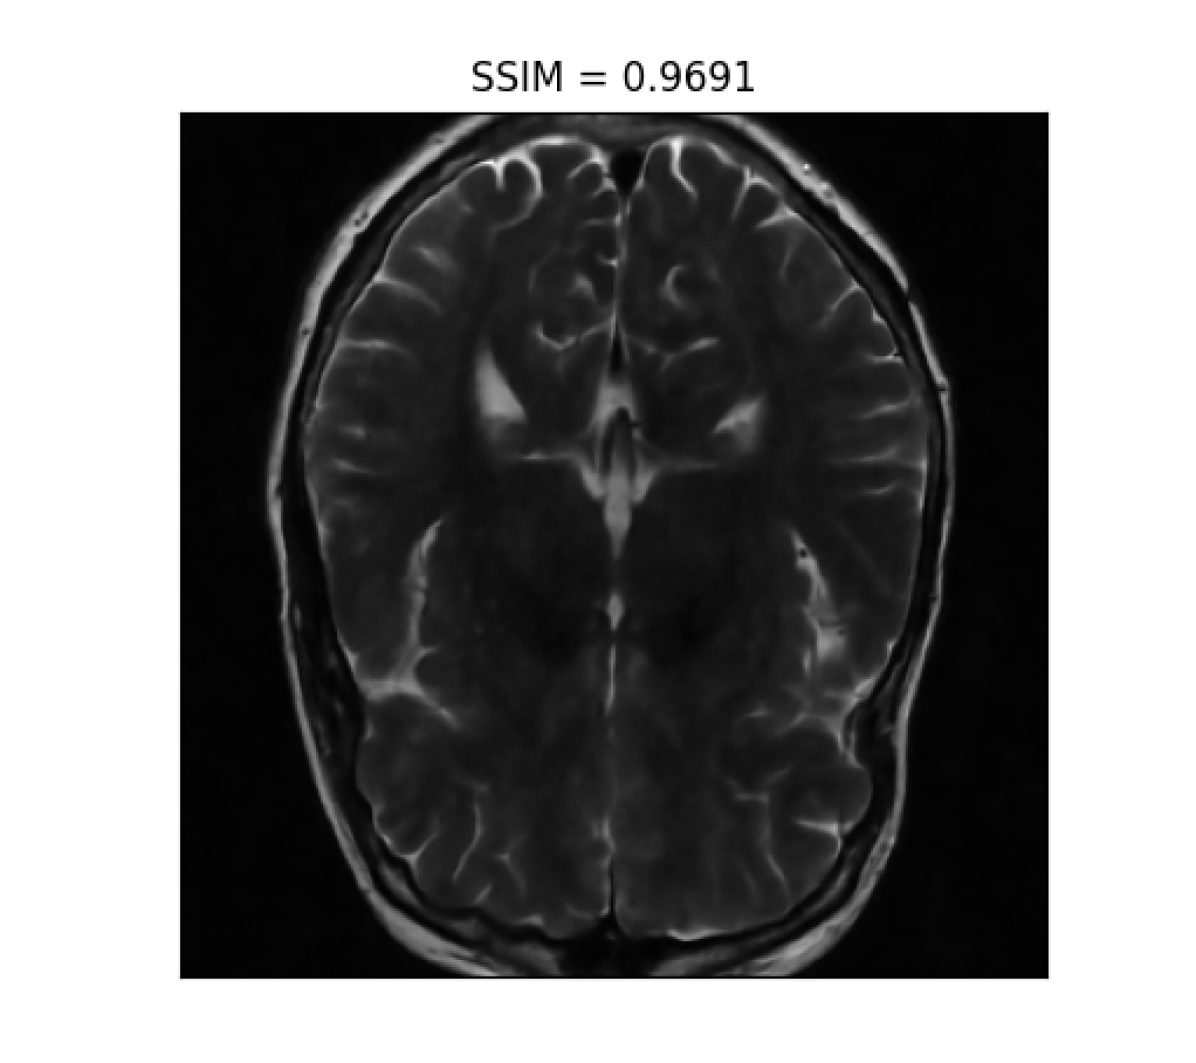

III-B2 Qualitative results

For visual inspection, we present the results of image reconstruction from data undersampled using SPARKLING trajectories generated for various target densities in Fig. 3 (T1subscriptT1\text{T}_{1}-w images) and Fig. 4 (T2subscriptT2\text{T}_{2}-w images). For the sake of space, we only report the best reconstruction results, i.e. with NC-PDNet. For T1subscriptT1\text{T}_{1}-weighted contrast, we show that all methods give similarly performing results, however 𝝆vdssubscript𝝆𝑣𝑑𝑠\boldsymbol{\rm\rho}_{vds} and 𝝆lbsubscript𝝆𝑙𝑏\boldsymbol{\rm\rho}_{lb} provide the best SSIM scores. Further, we observe that in this case, 𝝆vdssubscript𝝆𝑣𝑑𝑠\boldsymbol{\rm\rho}_{vds} is slightly better than 𝝆lbsubscript𝝆𝑙𝑏\boldsymbol{\rm\rho}_{lb}. On the contrary, for T2subscriptT2\text{T}_{2}-w contrast, 𝝆lbsubscript𝝆𝑙𝑏\boldsymbol{\rm\rho}_{lb} outperforms the other densities as reflected both visually in Fig. 4 and quantitatively (see Fig. 2).

Reference T2subscript𝑇2T_{2}-w Image (i) 𝝆vdssubscript𝝆𝑣𝑑𝑠\boldsymbol{\rm\rho}_{vds} (ii) 𝝆sbsubscript𝝆𝑠𝑏\boldsymbol{\rm\rho}_{sb} (iii) 𝝆lsbsubscript𝝆𝑙𝑠𝑏\boldsymbol{\rm\rho}_{lsb} (iii) 𝝆lbsubscript𝝆𝑙𝑏\boldsymbol{\rm\rho}_{lb}

Refer to caption Refer to caption Refer to caption Refer to caption Refer to caption

Figure 4: NC-PDNet-based image reconstruction for retrospective T2𝑇2T2-w imaging with slice 555 in file_brain_AXT2_200_2000019.h5 from validation data in fastMRI dataset for different target sampling densities.